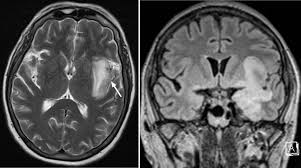

Mri Brain Hsv Encephalitis / Magnetic Resonance Imaging And Computerized Tomography Scanning Of Herpes Simplex Encephalitis In Journal Of Neurosurgery Volume 67 Issue 4 1987 / Encephalitis in the immunocompromised host.. Having said that, mri with contrast is considered the most sensitive imaging modality, and findings are present in over half of individuals 8. Initially clinical and brain mri findings were in favor of herpes simplex virus (hsv) encephalitis. Pregnancy the most common cause of encephalitis in newborns is vaginal delivery from a mother who is infected with herpes simplex virus 2 (hsv 2). Misra uk, hashmi aa, kalita j. The study analysed serially acquired magnetic resonance images (mri), of patients with.

Initially clinical and brain mri findings were in favor of herpes simplex virus (hsv) encephalitis. Clinical, magnetic resonance imaging, and electroencephalographic findings in paraneoplastic limbic encephalitis. Brain mri—increased t2 signal intensity in frontotemporal region → viral (hsv) encephalitis. Having said that, mri with contrast is considered the most sensitive imaging modality, and findings are present in over half of individuals 8. Pregnancy the most common cause of encephalitis in newborns is vaginal delivery from a mother who is infected with herpes simplex virus 2 (hsv 2).

Encephalitis in the immunocompromised host. Its symptoms are fever, confusion, coma, and seizures. Clinical, magnetic resonance imaging, and electroencephalographic findings in paraneoplastic limbic encephalitis. Alpha coma in japanese encephalitis. In children older than 3 months and in adults brain biopsy: Pregnancy the most common cause of encephalitis in newborns is vaginal delivery from a mother who is infected with herpes simplex virus 2 (hsv 2). Mri is the imaging of choice in suspected cases of viral encephalitis, although ct scanning may be used where mri facilities are not available. Herpes simplex encephalitis occurs as 2 distinct entities: Brain mri—increased t2 signal intensity in frontotemporal region → viral (hsv) encephalitis. • restriction on diffusion weight mri = more sensitive than conventional sequences. Hsv pcr and other infectious studies from the serum and csf were negative. Initial brain ct scanning was unremarkable but a subsequent mri scan showed features consistent with herpes simplex virus encephalitis. Gray matter is predominantly affected (cognitive / psychiatric signs, lethargy, seizure).

Herpes Simplex Virus Encephalitis Neurology Learning Network from www.neurologylearningnetwork.com Brain changes in herpes simplex virus (hsv). Brain mri is shown in fig. Brain mri—increased t2 signal intensity in frontotemporal region → viral (hsv) encephalitis. A case of granulomatous hsv encephalitis: Dhawan a, kecskes z, jyoti r, kent al. Alpha coma in japanese encephalitis. Contrast enhancement is uncommon during the first week of the disease. Encephalitis caused by hsv type 1 is rare but can result in significant brain damage or death.

Brain changes in herpes simplex virus (hsv). Encephalitis in the immunocompromised host. Hsv pcr and other infectious studies from the serum and csf were negative. Severe infection, particularly untreated herpes simplex virus (hsv) encephalitis, can cause brain hemorrhagic necrosis. Pregnancy the most common cause of encephalitis in newborns is vaginal delivery from a mother who is infected with herpes simplex virus 2 (hsv 2). Alpha coma in japanese encephalitis. Contrast enhancement is uncommon during the first week of the disease. Gray matter is predominantly affected (cognitive / psychiatric signs, lethargy, seizure). Diagnostic uncertainty and empirical management in pcr negative encephalitis. The study analysed serially acquired magnetic resonance images (mri), of patients with acute hsv encephalitis who had neuroimaging repeated within four weeks of the first scan. In children older than 3 months and in adults brain biopsy: • restriction on diffusion weight mri = more sensitive than conventional sequences. Mri is the imaging of choice in suspected cases of viral encephalitis, although ct scanning may be used where mri facilities are not available.